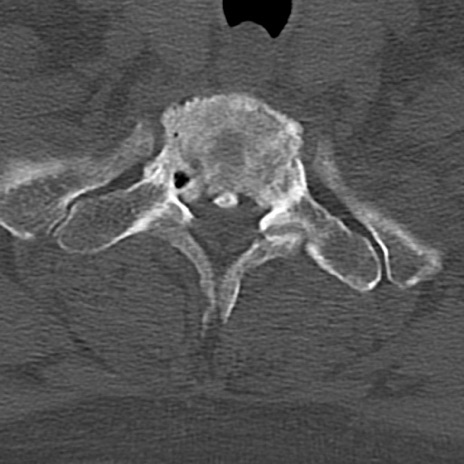

頚椎CT

横断像